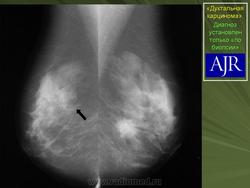

Инвазивная (или инфильтрирующая) протоковая карцинома – это наиболее часто встречающаяся форма рака молочной железы. Она составляет около 80 % из всех форм. В отличие от протоковой карциномы in situ, инвазивная карцинома характеризуется тем, что раковый процесс уже вышел за пределы молочного протока и распространяется на нормальные ткани молочной железы. Характерной особенностью инвазивной протоковой карциномы является очень твёрдая припухлость с неровными краями, которая спаяна с окружающим тканям. Сосок молочной железы или кожа вокруг него может быть втянута.

Часто на маммограммах в области опухоли выявляются микрокальцинаты, что связано с том, что в опухоли происходит омертвление ее клеток (некроз), которые в последствие пропитываются солями кальция. Опухоль при инвазивной карциноме может быть различных размеров, и у клеток может быть различное время деления, так что некоторые клетки растут быстрее других.